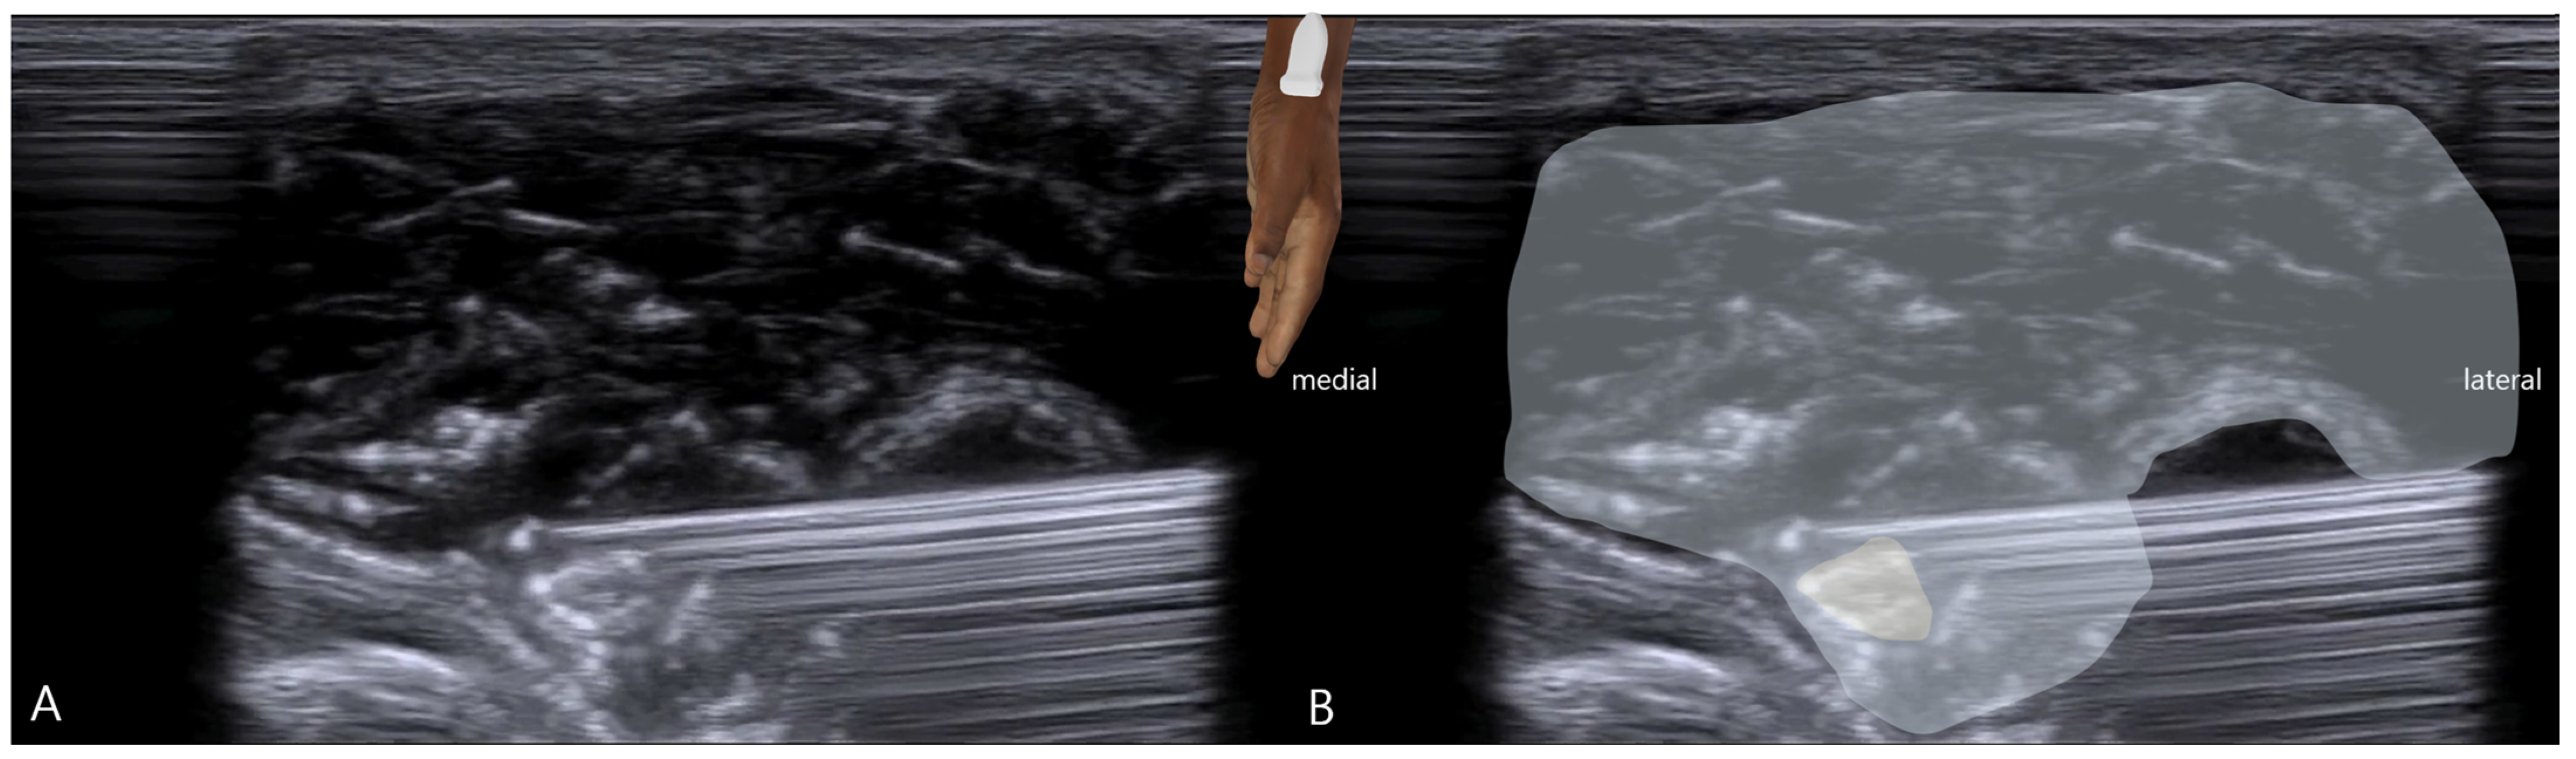

- Static Imaging: Transverse scans at the anatomical snuffbox revealed focal enlargement and loss of the normal fascicular echotexture of the SBRN on the symptomatic left side. The cross-sectional area (CSA) was measured at 0.13 cm2, significantly larger than the 0.08 cm2 on the asymptomatic right side (Figure 1). Power Doppler imaging showed mild hypervascularity around the left SBRN, suggesting ongoing inflammation.